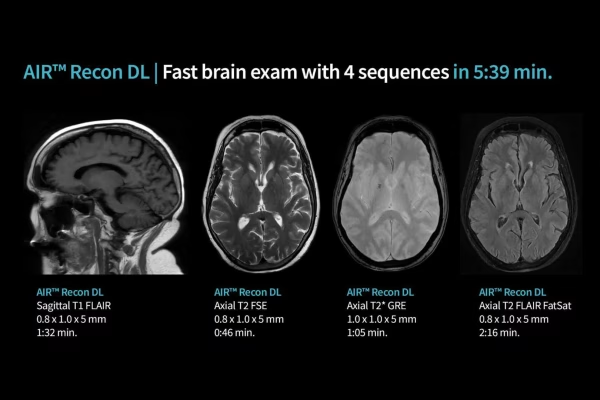

IRM GE Signa Explorer 1.5T